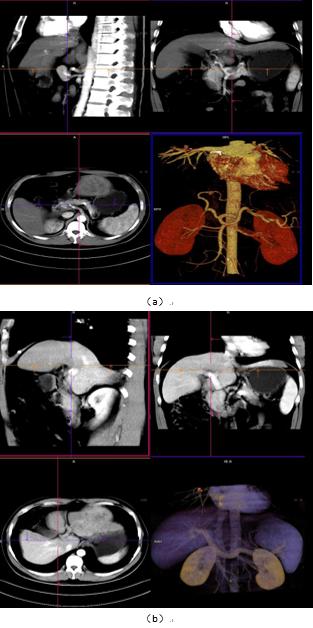

图 1 成像方式是目前大多数医院常规采取的扫描方式,满足对疾病的诊断,我中心当前采用的也是此类扫描方式,主要适用于常规检查、诊断,临床需求不单纯是提供诊断、还需要了解病灶与比邻组织器官关系,尤其是与大血管间的关系,制定最优化的手术方案,更快捷、安全、有效的进行手术治疗,但普通扫描在血管区分上欠佳。

图 1: 中心常规肝脏 CT 增强动脉、门脉显像(VRT/MPR)

图 2:一体化成像扫描肝动脉、门脉显像(VRT/MPR)